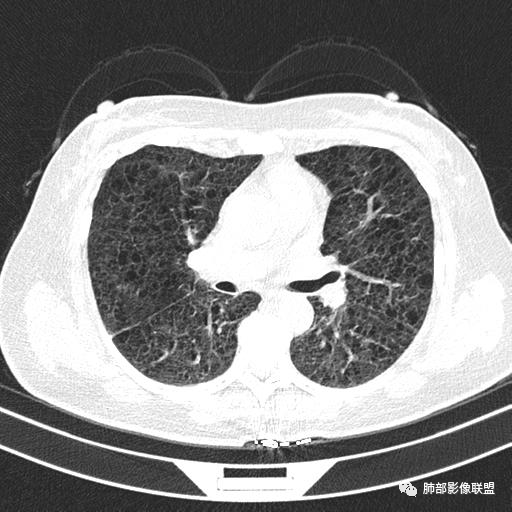

CT平扫示双肺弥漫分布大小不等囊状薄壁透光区,无内、中、外带分布差异,间质稍示增厚。拟LAM

中年女性育龄期妇女,咳嗽气喘,无吸烟史,有苯吸入史。影像:双肺弥漫均匀小囊腔,无明显分布优势,囊腔形态欠规则,壁薄,部分囊腔边缘血管征,伴双肺弥漫磨玻璃影,无结节,考虑lam,鉴别苯中毒肺损伤,囊腔多有分布优势,小叶中心分布为主,形态规整等

CT表现:双肺弥漫大小不等的薄壁囊腔,囊壁<2mm,外形规则,血管影多位于囊腔周围,囊腔之间肺组织正常,随着疾病进展到晚期,囊腔变大、增多,不可胜数,囊腔可融合成较大的囊,与肺气肿相似,形成间质性肺纤维化。部分病例可出现结节影。